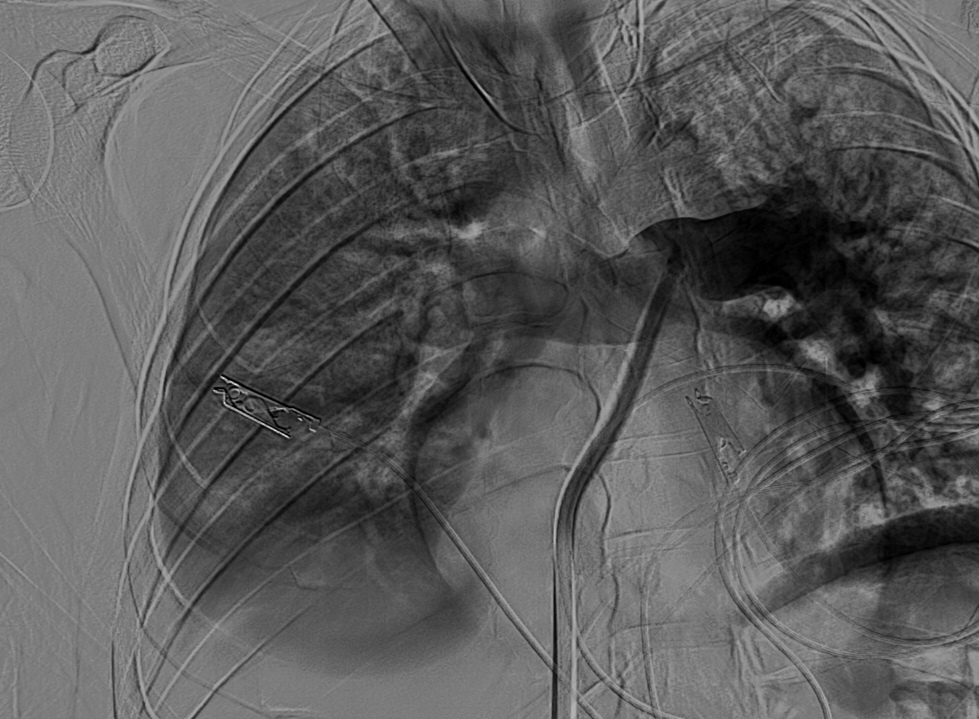

سجل مجمع الدمام الطبي أحد مكونات تجمع الشرقية الصحي ، إنجازاً طبياً نوعياً بعد نجاح فريق الأشعة التداخلية في إنقاذ حياة مريض كان يعاني من جلطة رئوية حادة وكبيرة شكّلت خطراً مباشراً على حياته ، وذلك باستخدام تقنية طبية متقدمة دون الحاجة إلى جراحة قلب مفتوح .

وكان المريض قد نُقل بشكل إسعافي من أحد المستشفيات وهو في حالة حرجة ، نتيجة معاناته من ضيق شديد في التنفس وانخفاض حاد في مستوى الأكسجين ، إثر انسداد كامل في الشريان الرئوي الرئيسي بسبب خثرات وريدية عميقة ظهرت بعد خضوعه لعملية منظار لمفصل الركبة.

وبفضل سرعة الاستجابة وجاهزية فريق الأشعة التداخلية جرى التدخل العلاجي العاجل وفتح الشريان الرئوي وسحب الجلطة بالكامل بدقة عالية ، ما أدى إلى تحسّن فوري في العلامات الحيوية واستقرار الحالة دون تسجيل أي مضاعفات.